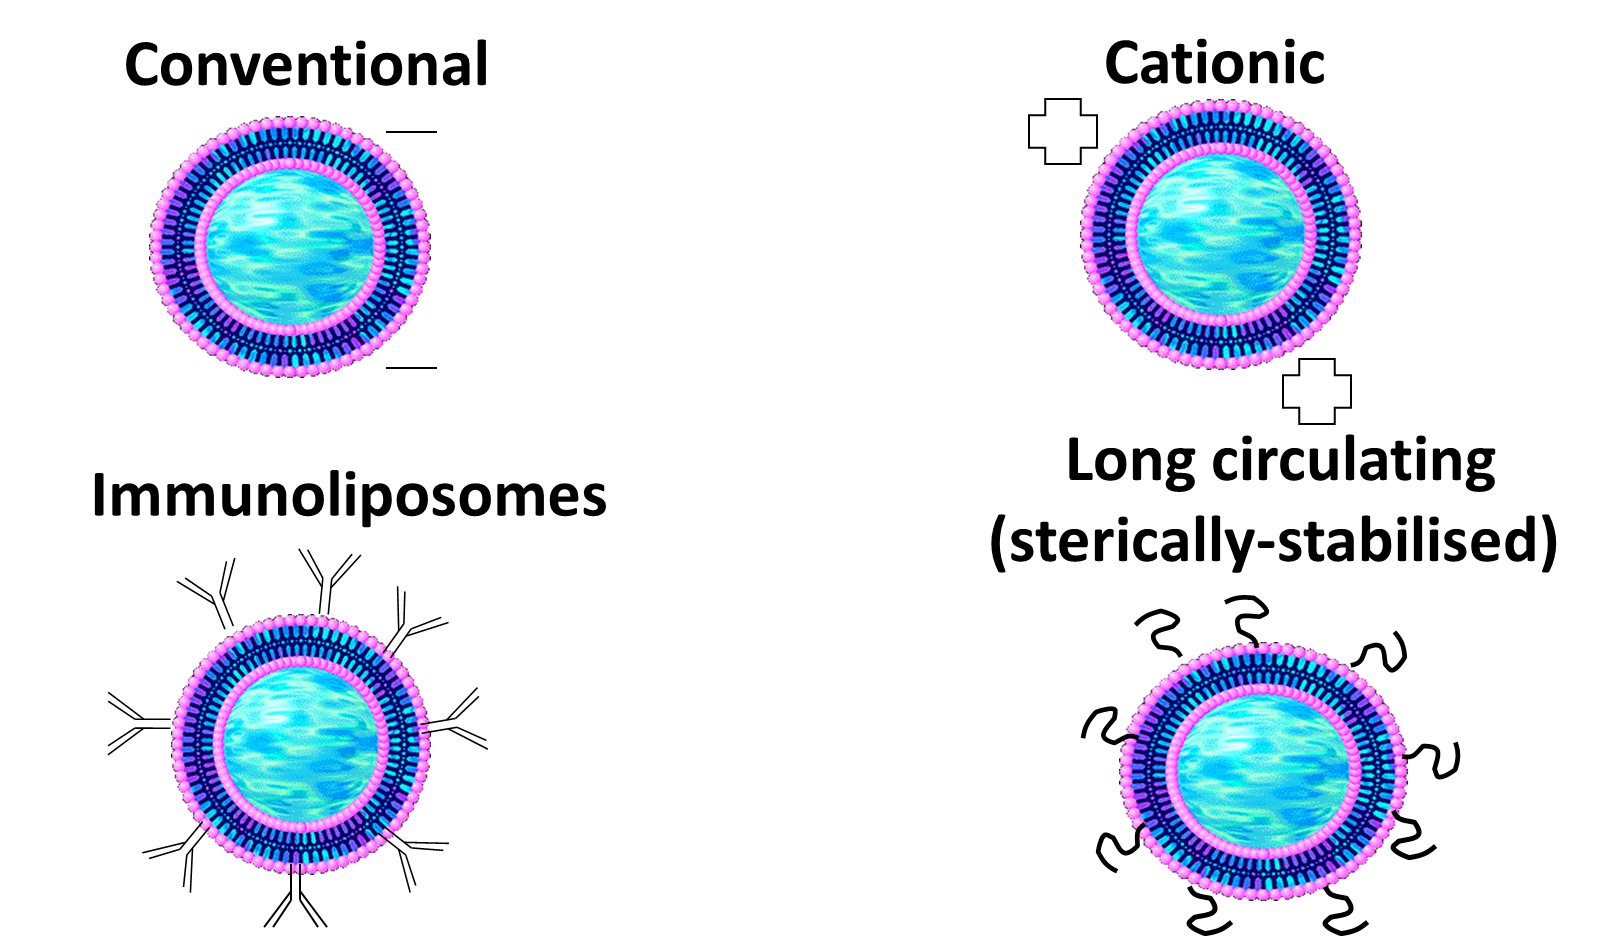

Classification of Liposomes

(according to their biological functionality)

Conventional liposomes are naturally negatively charged but can be modified to be catioinic. These have better interaction/Adsorption on the surface on the cells.

Immunoliposomes are targeted drug delivery using antibodies

Long circulating ones circulate for longer due to presence of PEG molecules.